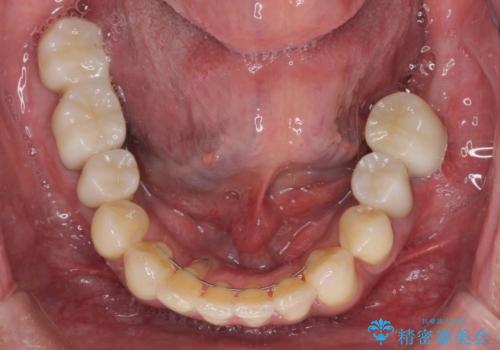

- 前歯がのデコボコや、奥歯に咬んだときに痛みがあるとのことで来院された患者様です。

全体的に問題が多く、全てをしっかりと治療したいとのことでした。

全体的に中等度の歯周病と診断されたため、歯周外科処置やインプラントによる咬合回復から進めて行き、矯正治療による歯列改善を行った後にオールセラミッククラウンにて補綴することとしました。

歯槽骨の再生治療を行ったため、外科処置後の静置期間がながくなり、4年弱の治療期間となりました。

初診来院時には矯正治療を行うことは想像していなかったようで、治療後には咬みやすさだけでなく、前歯が大変審美的に仕上がり、患者様には大変満足していただきました。